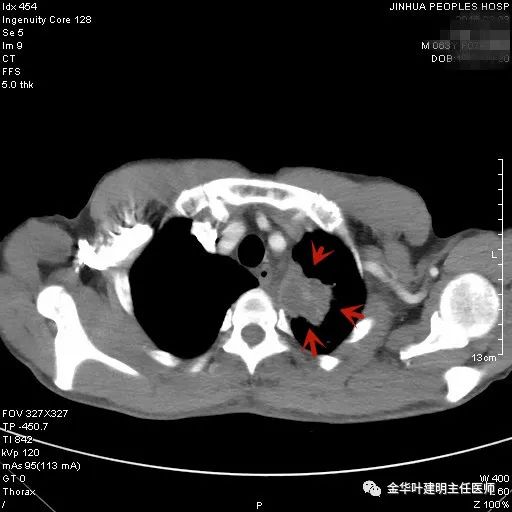

上图是结核,但这么明显的左上肺占位,谁又能从影像上排除它是肺癌呢?当然回头看,病灶中间密度低(可能液性)、周围一圈强化明显些、与纵隔组织关系密切但没有明显侵犯,界限仍然清楚,是有良性可能的。